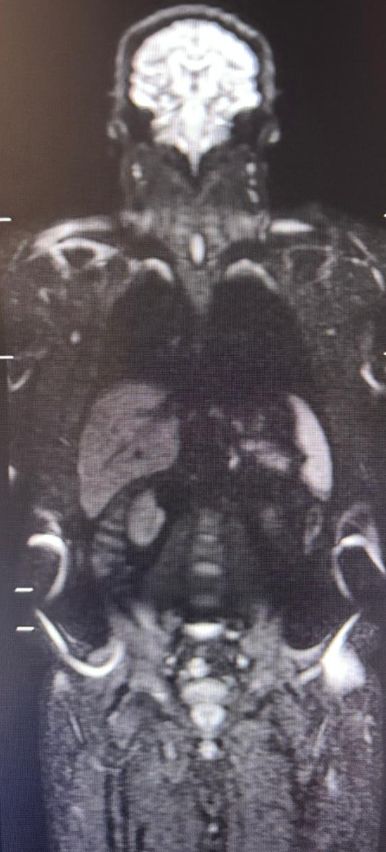

Ressonância magnética de corpo inteiro

A ressonância magnética de corpo inteiro (RM de corpo inteiro, ou WB-MRI) se consolidou como uma das ferramentas mais relevantes da imagem oncológica moderna. Trata-se de um método sem radiação ionizante, com excelente contraste tecidual e grande sensibilidade para detectar doença em múltiplos segmentos do corpo. No entanto, embora o nome do exame seja o mesmo, seu papel muda de forma importante conforme a indicação clínica. Isso fica especialmente claro quando comparamos sua aplicação na hematologia, particularmente no mieloma múltiplo, com seu uso na oncologia de vigilância, como no rastreio de pacientes com síndrome de Li-Fraumeni.

No mieloma múltiplo, a RM de corpo inteiro é um exame desenhado principalmente para avaliar a medula óssea e o esqueleto, identificando infiltração difusa, lesões focais, comprometimento cortical, doença paramedular e, em alguns casos, extensão extramedular. Nessa situação, o exame faz parte do raciocínio diagnóstico, do estadiamento e também da avaliação de resposta terapêutica, com protocolos estruturados dentro da lógica do MY-RADS, que padroniza aquisição, interpretação e seguimento.

Na prática hematológica, especialmente no mieloma múltiplo, a RM de corpo inteiro é extremamente útil para detectar doença que pode não ser suficientemente caracterizada por outros métodos. O exame valoriza muito a medula óssea, e por isso as sequências de difusão (DWI) e os mapas ADC têm papel central. A difusão ajuda tanto na detecção de lesões focais quanto na avaliação de atividade de doença e de resposta terapêutica, motivo pelo qual ela se tornou uma das bases do protocolo contemporâneo de mieloma.

Além da difusão, as sequências T1 e STIR são fundamentais para mapear substituição medular, edema, infiltração e alterações estruturais do esqueleto axial e apendicular. O exame, portanto, não é apenas uma “varredura do corpo”, mas um método especializado para responder a perguntas muito específicas da doença hematológica.